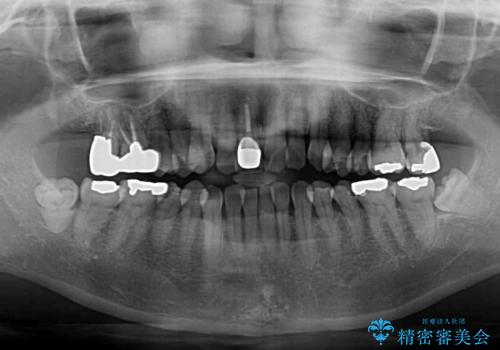

- 前歯のデコボコと口を開けたときに見える銀歯を気にして来院された患者様です。

矯正治療後に銀歯をセラミッククラウンなどに置き換えていくと、どうしても後戻りを起こしてしまうため、矯正治療が概ね終了した時点で銀歯を全てセラミックとし、最後に仕上げでインビザラインにを用いて細かいデコボコを改善していくこととしました。